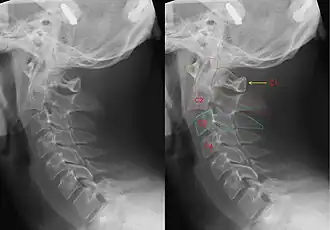

Röntgenfoto van de halswervelkolom met een hangman's fracture, hier ontstaan door een ongeval. Links zonder, rechts met annotatie. Duidelijk is te zien dat C2 (rode markering) naar voren is verschoven t.o.v. C3 (blauwe markering). | ||||

Dit type breuk wordt veroorzaakt door een plotselinge extreme overstrekking (hyperextensie) van de nek, eventueel ook gepaard gaande met een grote trekkracht langs de lengte-as van het lichaam. Door deze geweldsinwerking kan een breuk optreden in de axis (tweede halswervel). Daardoor kunnen nekwervels hun normale onderlinge samenhang verliezen en ten opzichte van elkaar gaan verschuiven, waarbij dan meestal de tweede nekwervel voorwaarts schuift ten opzichte van de derde. Daardoor kan het ruggenmerg ingeklemd of zelfs doorsneden worden: een hoog-cervicale dwarslaesie. Bij een dergelijk letsel treedt onmiddellijk een dodelijke verlamming op van het gehele lichaam inclusief de ademhalingsspieren, zodat het slachtoffer niet meer kan bewegen en dus ook niet ademen.